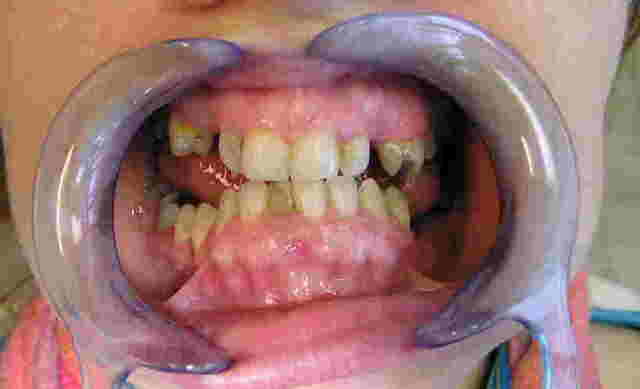

Patiente, environ 30 ans,reçue cette semaine, avec pour motif de consultation une réhabilitation complète de sa bouche + motif esthétique.

Quelques soins à réaliser, ce qui n'est pas un problème, par contre l'occlusion est particulièrement étrange.

Elle se positionne spontanément comme sur les 1ères photos, et je n'ai pas pu la manipuler plus en arrière. En articulé inversé, je retrouve une hauteur normale mais cette position lui cause des douleurs aux ATM.

Claquements bilatéraux aux niveaux des ATM, et un trajet de fermeture en baillonette avec décrochement à droite.

Sur la pano on retrouve cette drôle de mandibule... Infra alvéolie molaire et supra incisive...

Bonjour,ce qu'il est intéressant de noter, c'est l'aspect des procès alvéolaires, qui sont assez marqués et le fait que tu n'as pratiquement plus de calage occlusal postérieur avec en corollaire une propulsion mandibulaire pour aller mastiquer sur quelque chose.

Apparemment elle était en classe III.

La position qu'elle adopte spontanément est le bout à bout de la photo 1.

Je ne voudrai pas te contrer mais pour ce qui est de l'interposition linguale; sur la photo 1 on voit bien la langue qui déborde sur les dents postérieures restantes.

Pour ce qui est de la DV, il y a une raison pour laquelle elle adopte la position 1.